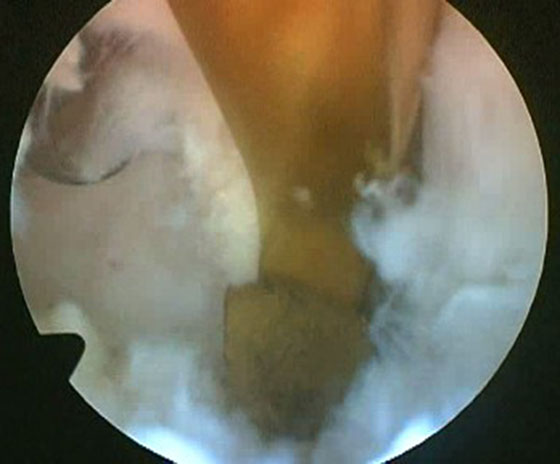

Se procede luego a realizar el portal posterointerno. Dado que no se reseca el remanente HPM, el espacio para acceder a la cápsula posterointerna se encuentra reducido, para ampliarlo realizamos una mínima “notchplastia” en la parte posterior del cóndilo interno (Fig. 4). Con la visión desde el portal anterointerno colocamos un switcher, de los utilizados en cirugía de hombro, desde el portal anterolateral ubicándolo entre el remanente ligamentario y el cóndilo interno (Fig. 5). Luego se pasa la cánula de irrigación guiada por el switcher y se accede con la óptica a la cápsula posterointerna, bajo visión directa colocamos una aguja espinal para localizar el portal, completando con bisturí para luego colocar la cánula de trabajo (Fig. 6). En este punto se vuelve a pasar el artroscopio al portal anterointerno, se introduce el shaver por la cánula del portal posterointerno, y se realiza la limpieza de la capsula posterior, siempre con la hoja de corte hacia anterior para evitar la lesión de estructuras vasculonerviosas. Se continúa alternando los portales anterointerno y posterointerno con visión, shaver, pinza basket y raspas de 90º, hasta completar la desinserción de cápsula posterior e identificar el remanente distal del ligamento sin afectar la inserción. En los casos en que la lesión ha sido en la sustancia colocamos la guía tibial distal a la inserción tibial (Fig. 7). Si la lesión ha comprometido la inserción tibial, levantamos la cicatriz que encontremos y colocamos la guía por debajo del remanente (Fig. 8). Para la introducción de la guía sin lesionar los remanentes ni el LCA se coloca la óptica en el portal anteroexterno y se controla el ingreso de la guía por el espacio entre el remanente y el cóndilo interno (Fig. 9). Se pasa el clavo guía, siempre cuidando de llegar en forma motorizada hasta contactar la cortical posterior y se completa el pasaje golpeando con martillo para evitar una salida brusca del mismo. Se pasa la fresa canulada del diámetro adecuado, protegiendo la emergencia de la misma con una cureta. Una vez completado el túnel tibial, se pasa un alambre o cable desde el orificio externo tibial hacia proximal, con visión en portal posterointerno, al ver emerger el alambre o cable por el orificio tibial posterior, se vuelve la óptica al portal anterointerno para controlar el pasaje de un grasper desde anteroexterno a través del intervalo entre HAL y LCA, y dirigirlo hacia posterior (Fig. 10); se vuelve con la óptica al portal posterointerno y se visualiza la recuperación del alambre o cable con el grasper hacia la parte anterior de la rodilla (Fig. 11). Se amplía el portal anteroexterno y se anuda la sutura tractora del injerto al alambre o cable, y traccionando desde el orificio distal del túnel tibial se hace ingresar el injerto en forma retrógrada a la articulación y, luego, al túnel tibial por su orificio posterior. En caso que se utilice el injerto de tendón cuadricipital la parte tendinosa irá al túnel tibial y el bloque óseo al femoral. Una vez ingresado el injerto al túnel tibial, se vuelve la óptica al portal anterointerno, en el portal anteroexterno tendremos la sutura tractora del extremo “femoral del injerto”, es aconsejable en este punto llevar el injerto lo más distal posible para tener mejor visión articular, enhebrar la sutura tractora en una cánula de unos 6 mm de diámetro, para asegurarse que la sutura tractora y la clavija pasasutura pasan por el mismo espacio sin incluir tejido sinovial o grasa retrorrotuliana (Fig. 12). Se procede a pasar la aguja pasasutura por el túnel femoral, saliendo por las partes blandas de la parte medial de la rodilla, se tracciona y se asciende el injerto colocándolo en el túnel femoral. En caso que el injerto tenga bloque óseo puede ser necesario redirigir el mismo para ubicarlo en el túnel femoral, para esto ubicamos la visión en el portal anteroexterno y por el portal anterointerno utilizamos el trocar romo o el palpador para realizar una polea y mejorar la tracción para que ingrese el taco óseo en el túnel femoral (Fig. 13). Luego se realiza la fijación femoral con tornillo de interferencia de titanio o biodegradable. A continuación liberamos el manguito neumático, porque creemos que produce un espasmo en los isquiotibiales que dificulta la reducción de la tibia, dejamos pasar unos minutos que utilizamos para colocar un tornillo maleolar con arandela, distal al orificio externo del túnel tibial para realizar una segunda fijación de la parte tibial. Preferimos hacerlo antes de colocar el tornillo interferencial, porque esto generará una presión hacia posterior de la tibia. Se realiza la reducción tibial en 90° de flexión de la rodilla, se tracciona del injerto y se coloca el tornillo de interferencia tibial, luego la sutura remanente (polyester 5) se anuda en el tornillo maleolar completando la 2da fijación. Por último se constata con una nueva visión articular la posición y tensión del injerto (Fig. 14).

Figura 14

Figura 15